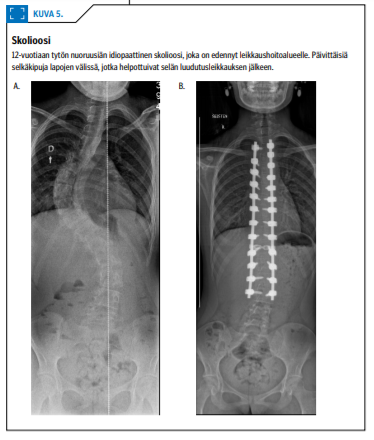

Idiopaattiseen skolioosiin tai Scheuermannin tautiin liittyy noin kolmasosalla lapsista selkäkipua, joka selkärangan luudutusleikkauksen jälkeen helpottuu merkittävästi (4) (kuva 5 «»7). Kivuliaan skolioosin taustalta tulee kuitenkin sulkea pois muut syyt. Muiden syiden todennäköisyys kasvaa, jos käyryys on epätyypillinen, esimerkiksi vasemmalle kupera rintarangan käyryys.